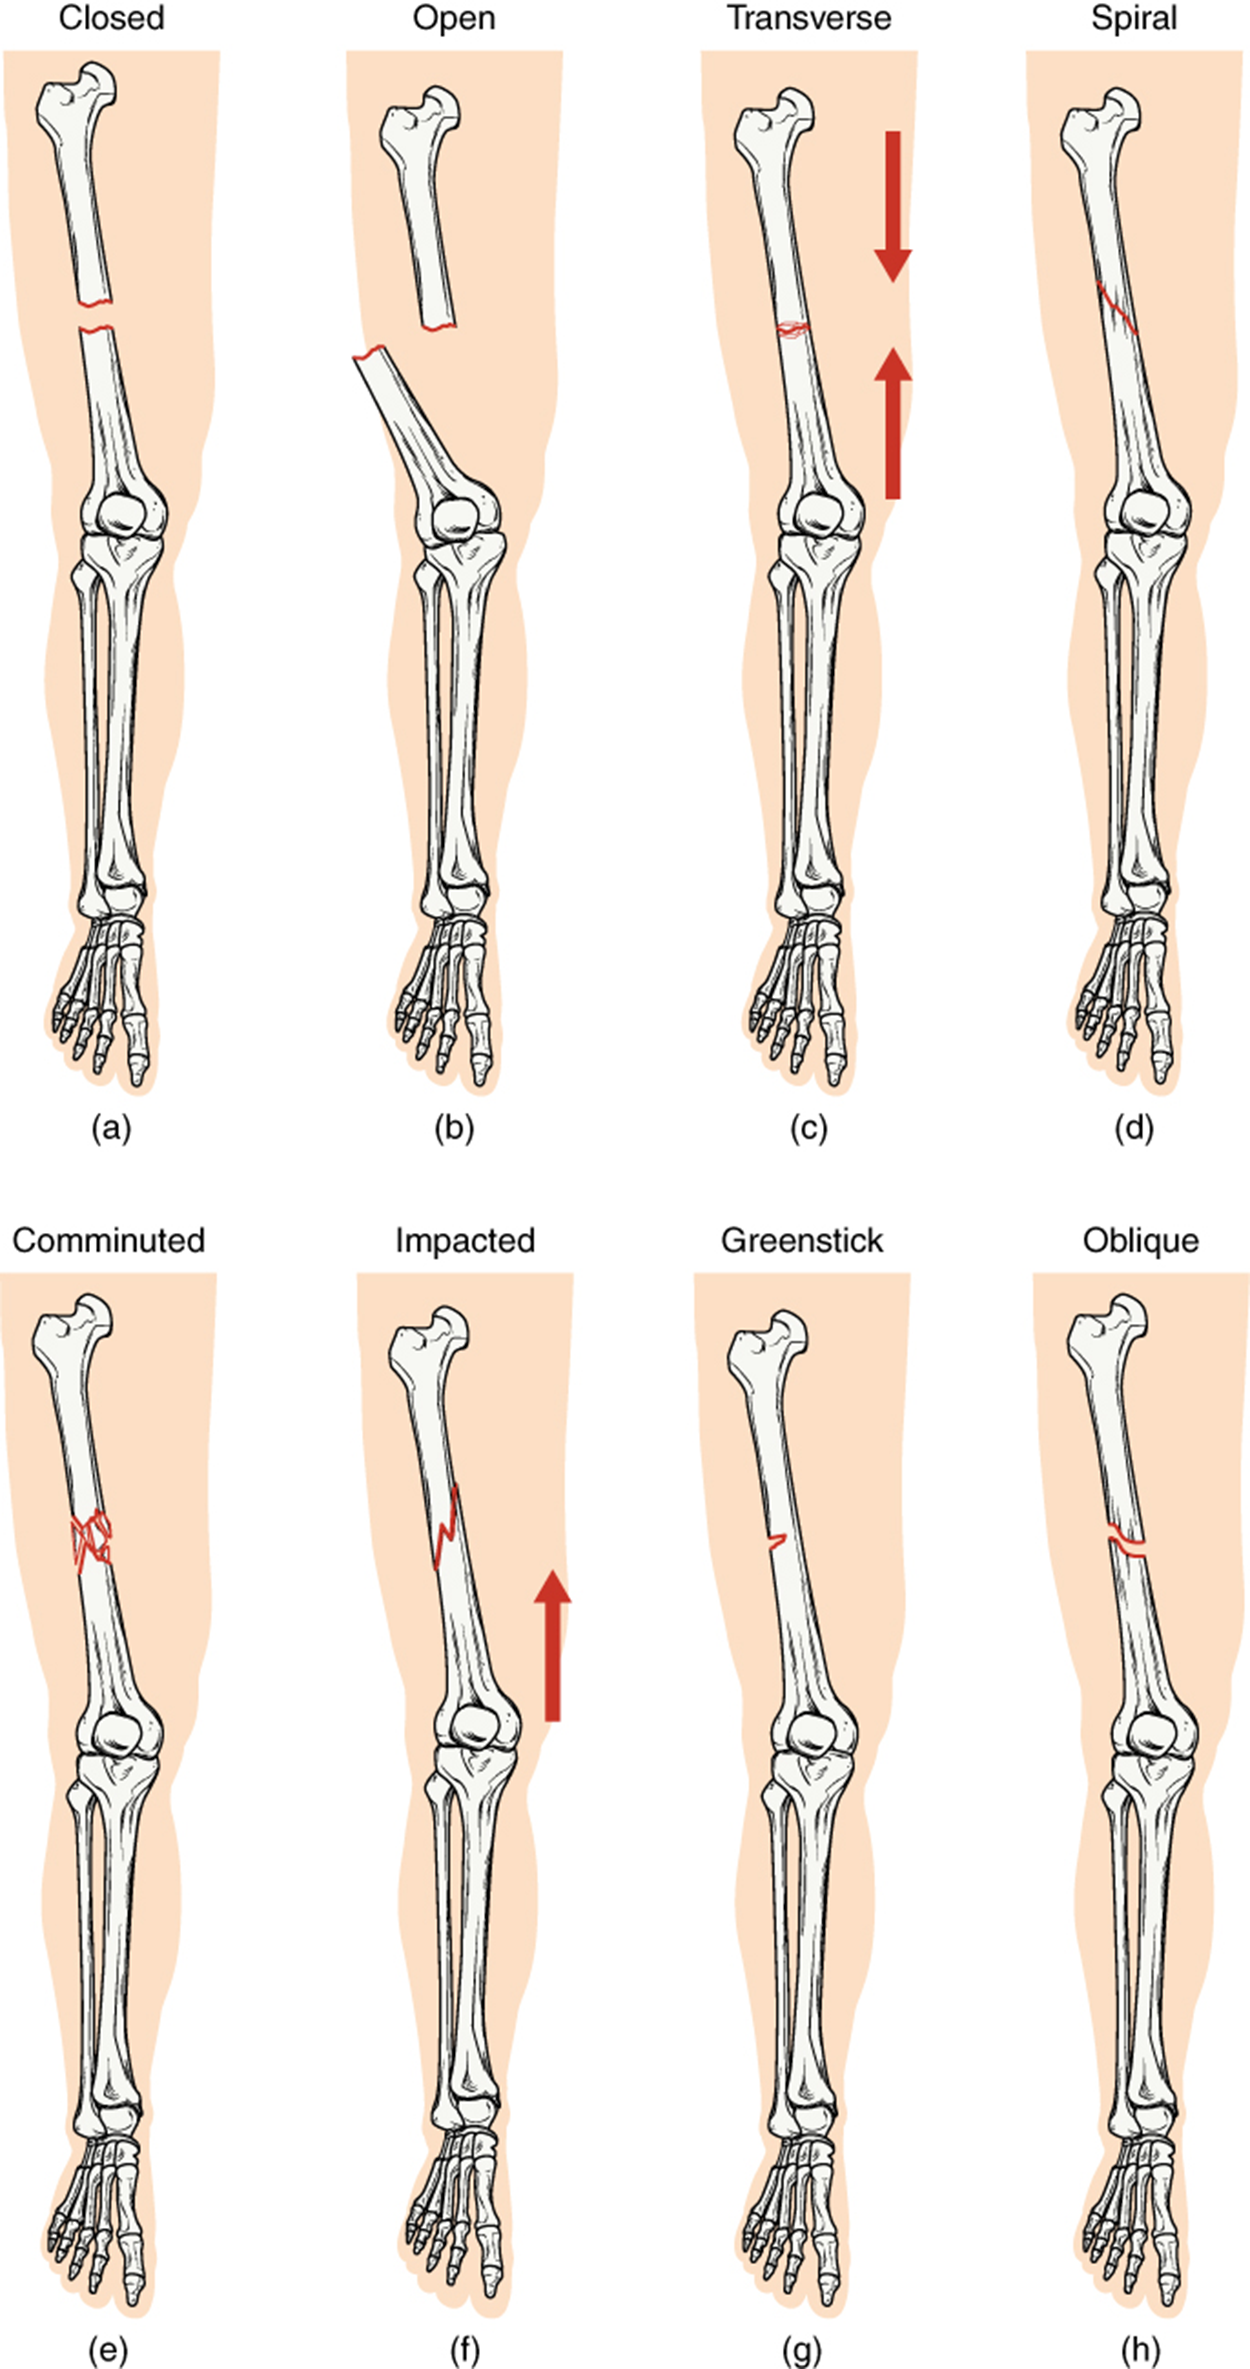

Fractures are classified by their complexity, location, and other features. The table below outlines common types of fractures. Some fractures may be described using more than one term because they may have features of more than one type (i.e., an open transverse fracture).

Types of Fractures—Compare healthy bone with different types of fractures: (a) closed fracture, (b) open fracture, (c) transverse fracture, (d) spiral fracture, (e) comminuted fracture, (f) impacted fracture, (g) greenstick fracture, and (h) oblique fracture.

Types of Fractures

Type of fracture Description

Closed (or Simple) Fracture A fracture in which the skin remains intact

Open (or Compound) Fracture A fracture in which at least one end of the broken bone tears through the skin; carries a high risk of infection

Transverse Fracture A fracture that occurs straight across the bone, perpendicular to the long axis of the bone

Spiral Fracture Bone segments are pulled apart as a result of a twisting motion

Comminuted Fracture Several breaks resulting in many small pieces between two large segments

Impacted Fracture One fragment is driven into the other, usually as a result of compression

Greenstick Fracture A partial fracture in which only one side of the bone is broken

Oblique Fracture A fracture that occurs at an angle that is not 90 degrees